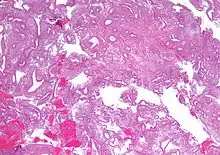

Micrograph showing simple endometrial hyperplasia, where the gland-to-stroma ratio is preserved but the glands have an irregular shape and/or are dilated. Endometrial biopsy. H&E stain.

Like other hyperplastic disorders, endometrial hyperplasia initially represents a physiological response of endometrial tissue to the growth-promoting actions of estrogen. However, the gland-forming cells of a hyperplastic endometrium may also undergo changes over time which predispose them to cancerous transformation. Several histopathology subtypes of endometrial hyperplasia are recognisable to the pathologist, with different therapeutic and prognostic implications.[3]